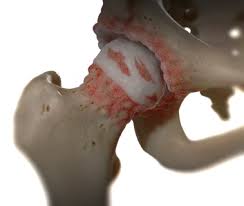

앉아 있을 때 느껴지는 불편감

고관절 통증은 걷거나 움직일 때뿐 아니라 가만히 앉아 있을 때도 나타날 수 있습니다.

• 오래 앉아 있으면 엉덩이 통증

• 의자에서 일어날 때 뻣뻣함

• 장시간 운전 후 통증

특히 장시간 앉아 있다가 처음 움직일 때 통증이 심해진다면 고관절 내부의 마찰이나 염증 가능성을 생각해볼 수 있습니다.